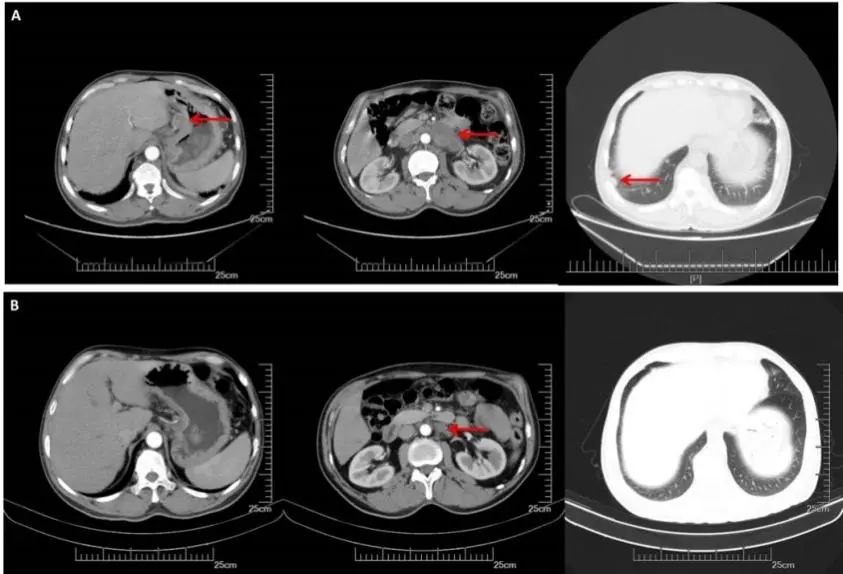

A:CT增强(2016.08.22): 胃体小弯侧增厚,肝胃间、腹膜后多发淋巴结转移,双肺多发转移。B:2周期化疗后CT增强(2016.10.19):胃壁增厚减轻,淋巴结明显缩小,双肺多发转移灶几乎消失

2、第2次MDT:该患者两个周期的一线治疗方案,双肺转移灶基本完全消失,腹腔淋巴结较前缩小,疗效评估接近PR,但目前仍然无根治的手术机会,建议继续SOX方案化疗,同时,仍要建议患者行HER2基因检测。但患者提出既往曾出现过呕血病史,惧怕再次出现呕血状况发生,遂强烈要求行手术治疗。